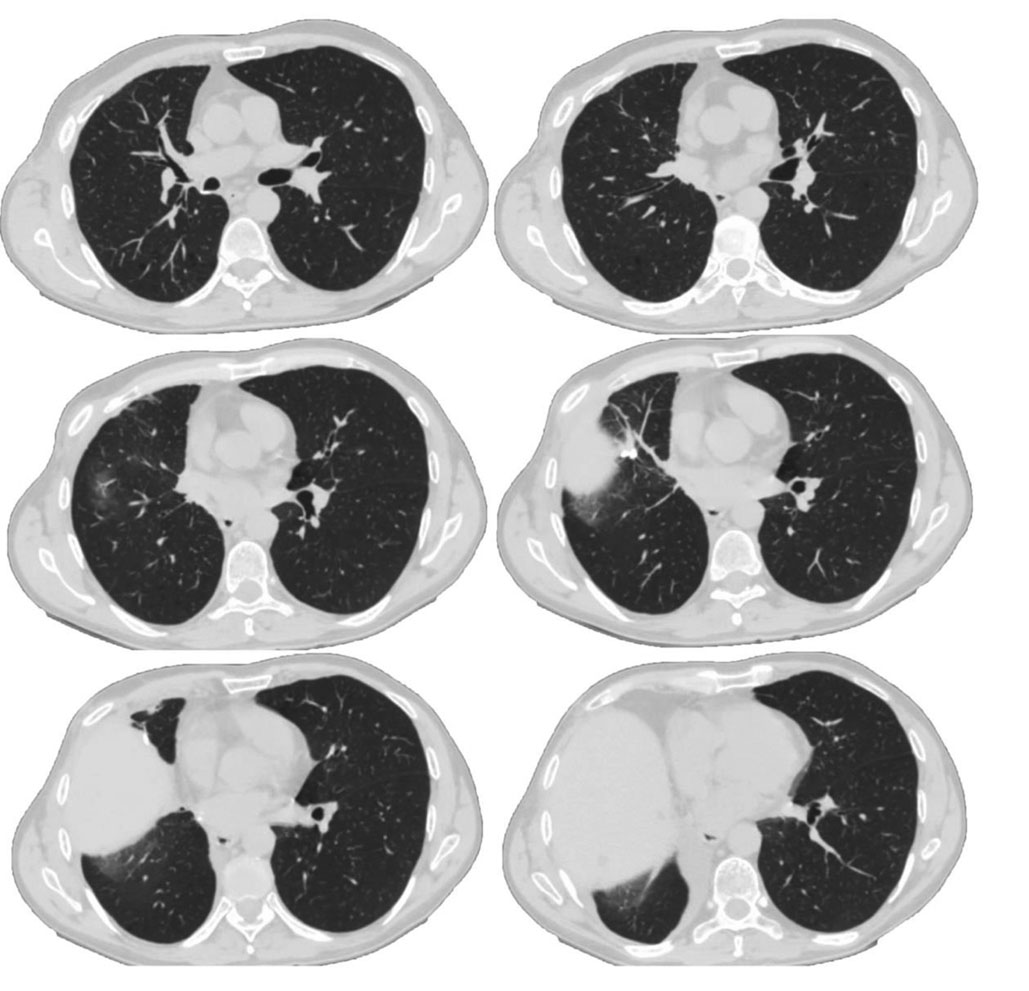

Пациент В., 60 лет, с длительным стажем курения в анамнезе (40 пачколет), без установленных диагнозов со стороны органов дыхания, обратился за медицинской помощью в стационар с жалобами на влажный кашель с отделением мокроты слизисто-гнойного характера, больше по утрам. Принимая во внимание неблагоприятную эпидобстановку, возраст, жалобы и анамнестические данные, была выполнена компьютерная томография груди. По данным первичной спиральной компьютерной томографии органов грудной клетки (СКТ ОГК) в области бифуркации сегментарных 8-го и 9-го бронхов перибронхиально определялось образование с нечеткими неровными контурами, размером 20 × 16 мм, включающее в себя лимфатический узел, 8-й бронх — с признаками сужения до 3 мм на протяжении 10 мм, 9-й бронх — без признаков сужения, соответствующие сегментарные артерии интимно прилежали к образованию, пневматизация легочной ткани — неравномерная за счет участков центрилобулярной и парасептальной эмфиземы в верхних долях обоих легких, дисковидный ателектаз в S10 правого легкого (рис. 1).

Рис. 1. Спиральная компьютерная томография органов грудной клетки пациента В. при первичном обследовании

Fig. 1. Spiral computed tomography of patient B’s chest organs during initial examination